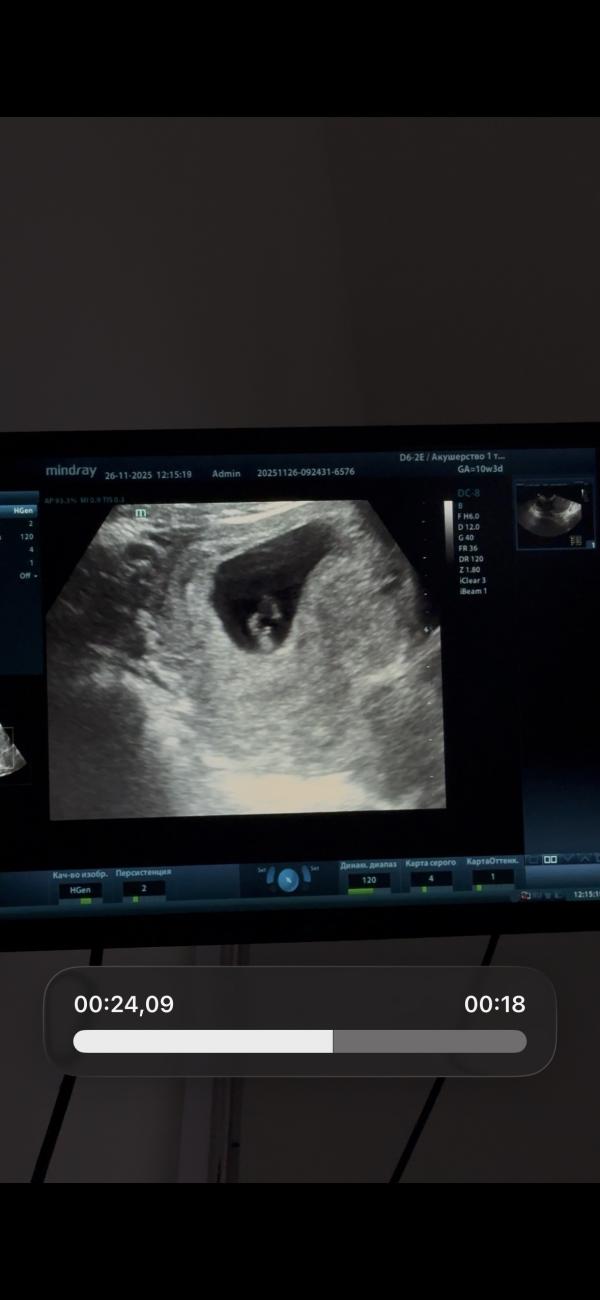

Полистайте карусель

И скажите

Мальчик это или девочка

😂

Тут не может быть ещё никаких яичек, тут тока бугорок, и то ещё рано судить, он может ещё подняться

@leyla.isl, ну в 10 недель яичек и писюна прям видно не будет по любому 😀